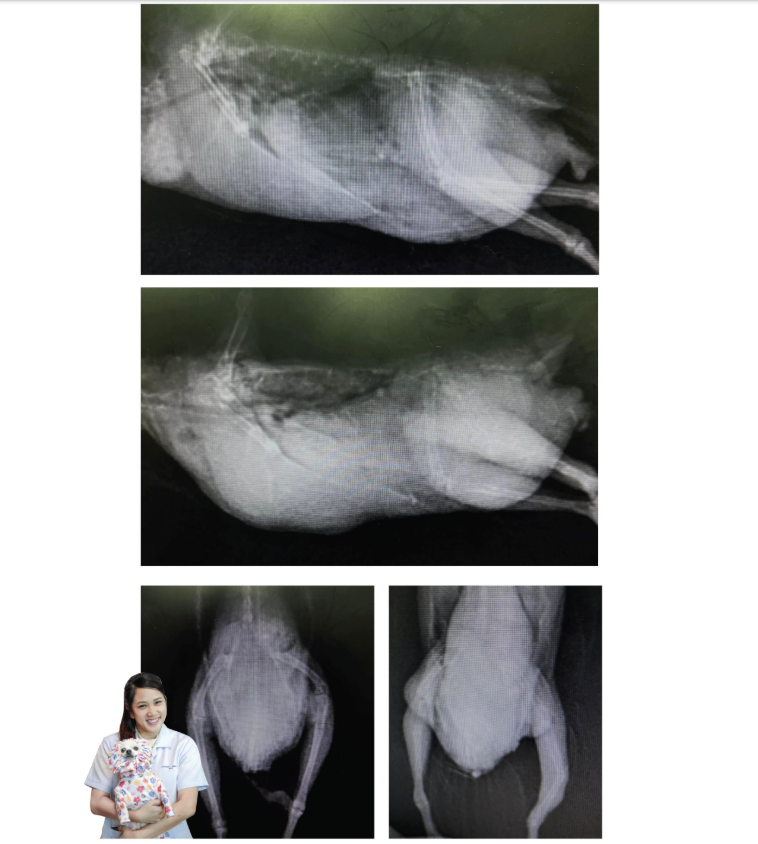

1. Egg Binding (Dystocia) Egg binding is a condition where a female bird is unable to pass an egg naturally. On an X-ray, this is clearly visible as an oval, calcified object (the egg) located in the lower abdominal or pelvic area.

X-ray Findings: In birds with MBD, the bones will appear "thin" or less "white" (decreased bone density) on the X-ray. In severe cases, you may see "pathological fractures" (broken bones that occur from normal movement because the bones are so fragile).

3. The "Thin-Shelled" Egg Sometimes the X-ray reveals an egg with a very faint or "ghost-like" shell. This indicates that the bird did not have enough calcium to form a proper shell, making the egg soft or fragile. This also makes it much harder for the bird to pass the egg because the uterus cannot grip and push a soft object effectively.